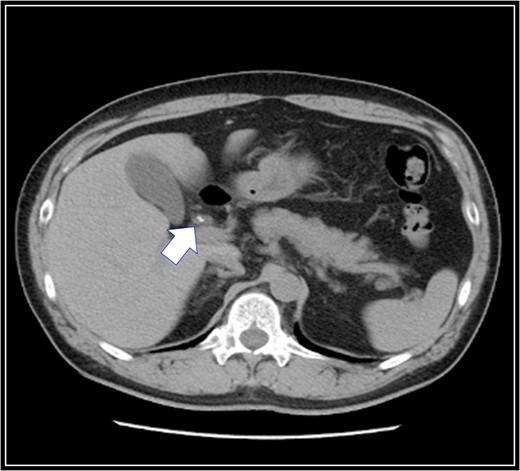

A 48-year-old Japanese man experienced abdominal pain after dinner. He underwent computed tomography (CT), and we observed stones in his cystic duct (Fig. 1). Hematological findings showed no liver dysfunction. A magnetic resonance cholangiopancreatography (MRCP) scan demonstrated that the right accessory hepatic duct branching from the cystic duct dominated an anterior segment of the right hepatic lobe (Fig. 2). Therefore, we diagnosed him as cholelithiasis with an anomalous biliary tract, and LC was planned.

Preoperative abdominal computed tomography scan. There are stones in his cystic duct (white arrow).